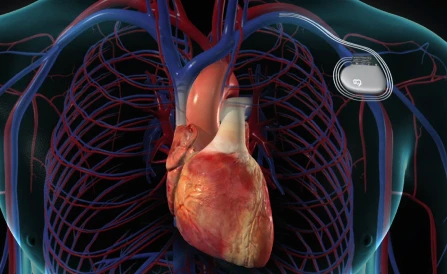

Pacemaker & ICD Implants

Advanced device implants to treat irregular heart rhythms, ensuring safe heartbeat control and protection against sudden cardiac arrest.

- Device Therapy: Pacemaker implantation, ICD (Implantable Cardioverter Defibrillator) implants, and advanced pacing therapies.

Pacemaker and ICD implants are safe, effective, and life-saving for patients with arrhythmias. Dr. Suhaimi specializes in device implantation with advanced monitoring to ensure optimal results.